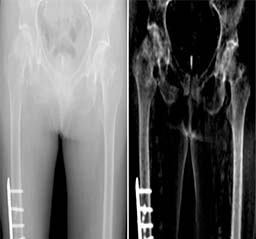

"Departmental Photos"